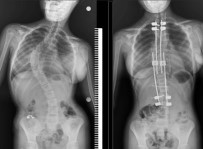

16 Ağustos 2022 Salı 16:36:19500 Bin Liralik Ameliyati 1 Kurus Vermeden Oldu

Samsun Egitim ve Arastirma Hastanesi’nde ilk defa 10 yasindaki bir çocuga skolyoz (omurga egriligi) ameliyati yapildi. Özel hastanelerde 300-500 bin TL arasinda yapilan bu ameliyat kamu hastanesinde ücret alinmadan basarili bir sekilde gerçeklestirildi.